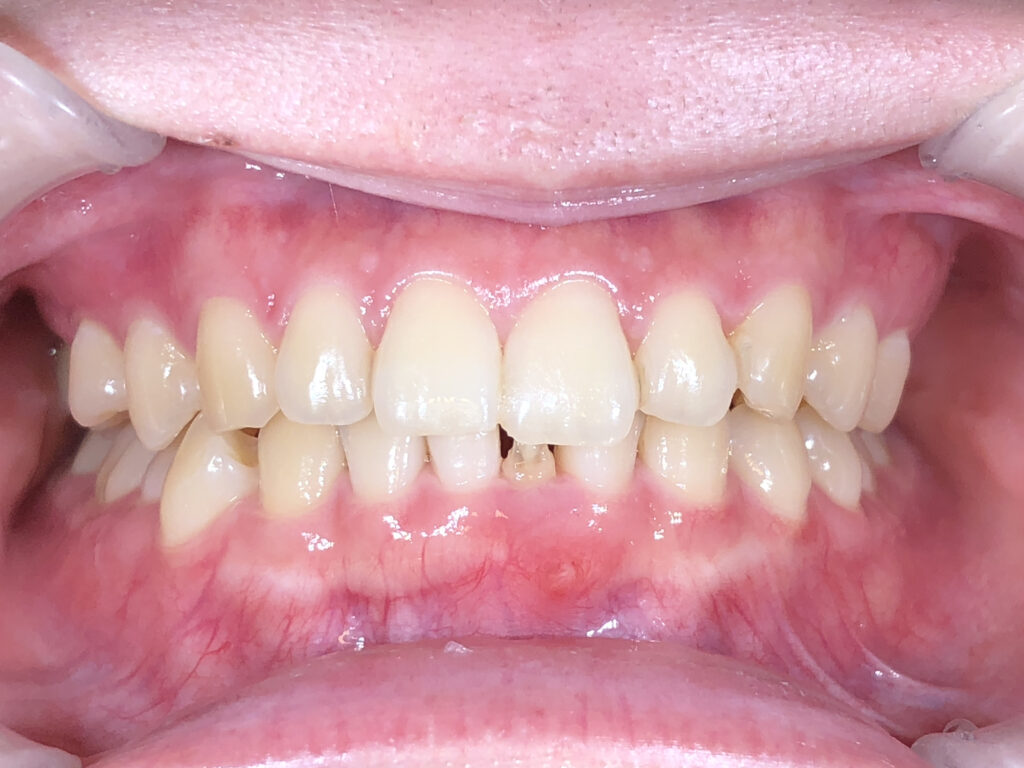

正面

治療前